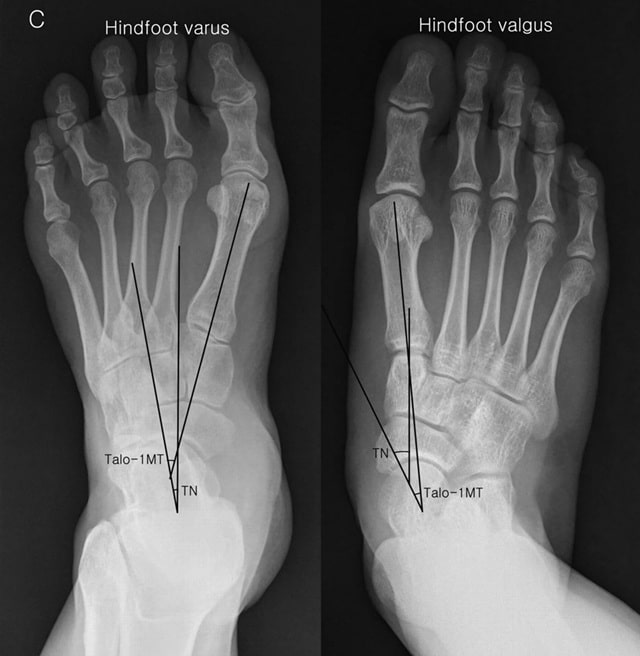

Сперва разберемся, что такое вальгус стопы. Это деформация, при которой средний отдел стопы заваливается вовнутрь, пальцы и пятки выгибаются наружу, а голени изгибаются дугой. Колени прижимаются друг к другу, поэтому вальгус также называют Х-образной деформацией. Чаще всего сопровождается плоскостопием. Вот, что такое вальгусная деформация стоп у детей и взрослых.

При варусной деформации происходит опора на внешнюю сторону стопы, носок повернут вовнутрь, расстояние между лодыжками уменьшается, а между коленями – увеличивается. Из-за этого варус называют О-образной деформацией. Она не всегда сопровождается плоскостопием. Патология у детей возникает по таким причинам: